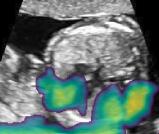

Fig. 6 compares the shadow confidence maps of the state-of-the-art methods and the proposed methods. RW and have the same parameters as used for Table I. The shadow confidence maps of the baseline, the proposed method and the proposedAG method are generated directly from input shadow images by confidence estimation networks. Overall, the proposed method and the proposedAG method achieve more visually reasonable shadow confidence estimation than the baseline and the state-of-the-art on different anatomical structures shown in Fig. 6. The proposed method and the proposedAG method are able to highlight multiple shadow regions while the RW algorithm shows limitations for most cases, especially for disjoint shadow regions.

Row I in Fig. 6 shows a fetal brain image from . The confidence estimation of shadow regions from the baseline, the proposed method and the proposedAG method are similarly accurate since we use fetal brain images to train the confidence estimation networks in these three methods. These outperform [16] and [22]. Rows (II-IV) in Fig. 6 show shadow confidence maps of non-brain anatomy from , including lips, abdominal and cardiac. The baseline failed on unseen data during inference. However, the proposed methods are able to generate accurate shadow confidence maps because of the generalized shadow features obtained by the shadow-seg module. Furthermore, the “Lips” example shows that our method is capable of detecting weaker shadow regions that have not been annotated in manual segmentation. This indicates that the confidence estimation network has learned general properties of shadow regions.